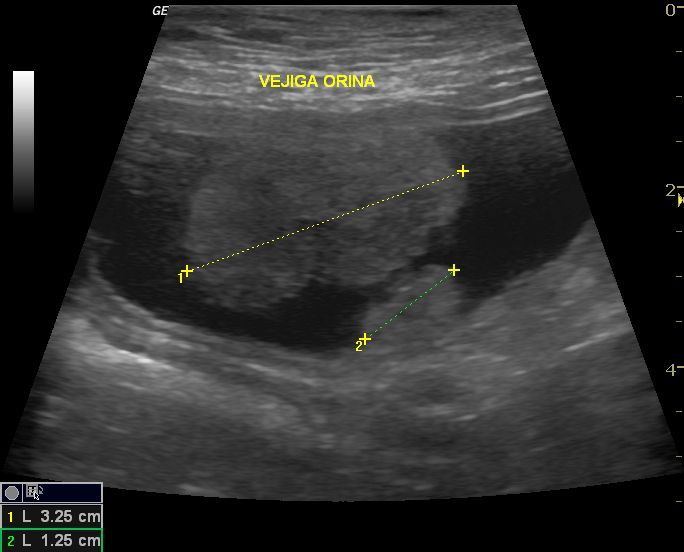

La Ecografía permite una exploración completa de los distintos órganos aportando datos objetivos para conseguir un diagnóstico preciso , establecer un tratamiento adecuado y realizar un seguimiento de cada caso.

La ecografía como diagnótico de gestación es a día de hoy el método más fiable durante el primer trimestre, además nos aporta datos para predecir la fecha de parto, y realizar un seguimiento del desarrollo de los fetos, pudiendo evaluar el estres fetal.